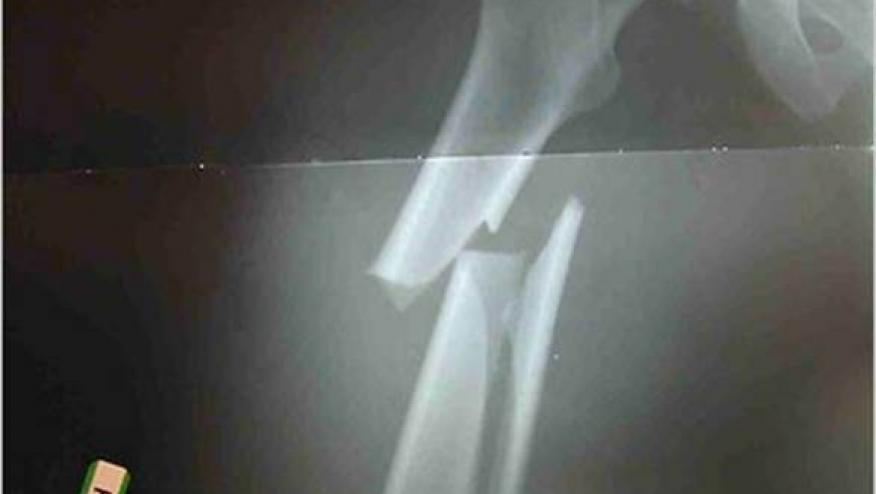

A large Swedish cohort study of hypertensive men and women presented at the 25th Scientific Meeting of the European Society of Hypertension, identitied a protective effect on osteoporotic fractures among current users of thiazide diuretic drugs independent of blood pressure level. This retrospective cohort study analysed data on 60,893 hypertensive patients between 2001 and 2008. By the end of the study, a total of 2,421 fractures occurred. The use of thiazide diuretics was significantly associated with a reduced risk of having an osteoporotic fracture (adjusted hazard ratio [HR], 0.88). Conversely, an increased risk of osteoporotic fractures was seen with the discontinuation of thiazides (HR, 1.17).